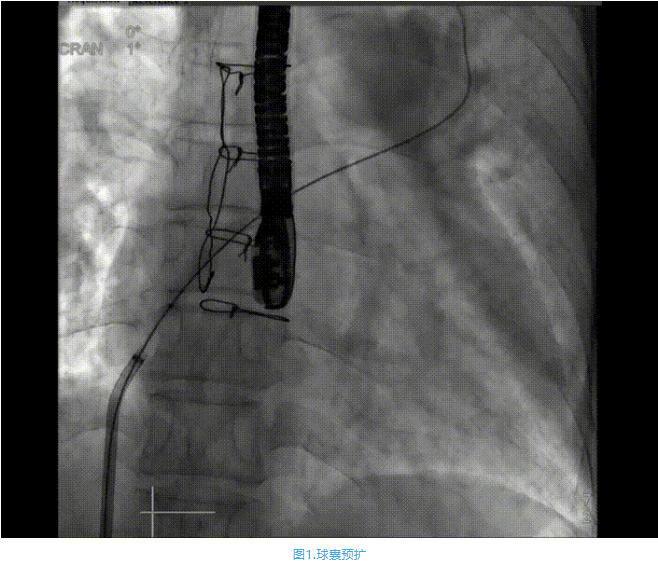

術(shù)中首先在局麻下穿刺股動脈、股靜脈,完成心導(dǎo)管檢查評估后轉(zhuǎn)為全麻,在食道超聲引導(dǎo)下穿刺房間隔,穿刺成功后將加硬導(dǎo)絲送入左上肺靜脈建立軌道,根據(jù)患者病情行球囊預(yù)擴張后植入6mm孔徑房間隔造孔支架,經(jīng)透視及食道超聲評估支架左右盤展開良好,夾持于房間隔兩側(cè),固定穩(wěn)定、位置良好,食道彩超顯示房水平右向左為主分流,分流孔直徑符合預(yù)期大小,心導(dǎo)管檢查評估達到預(yù)期效果,釋放造孔支架。術(shù)后12h患者下床活動,恢復(fù)順利,擬于近日完善術(shù)后評估后出院。